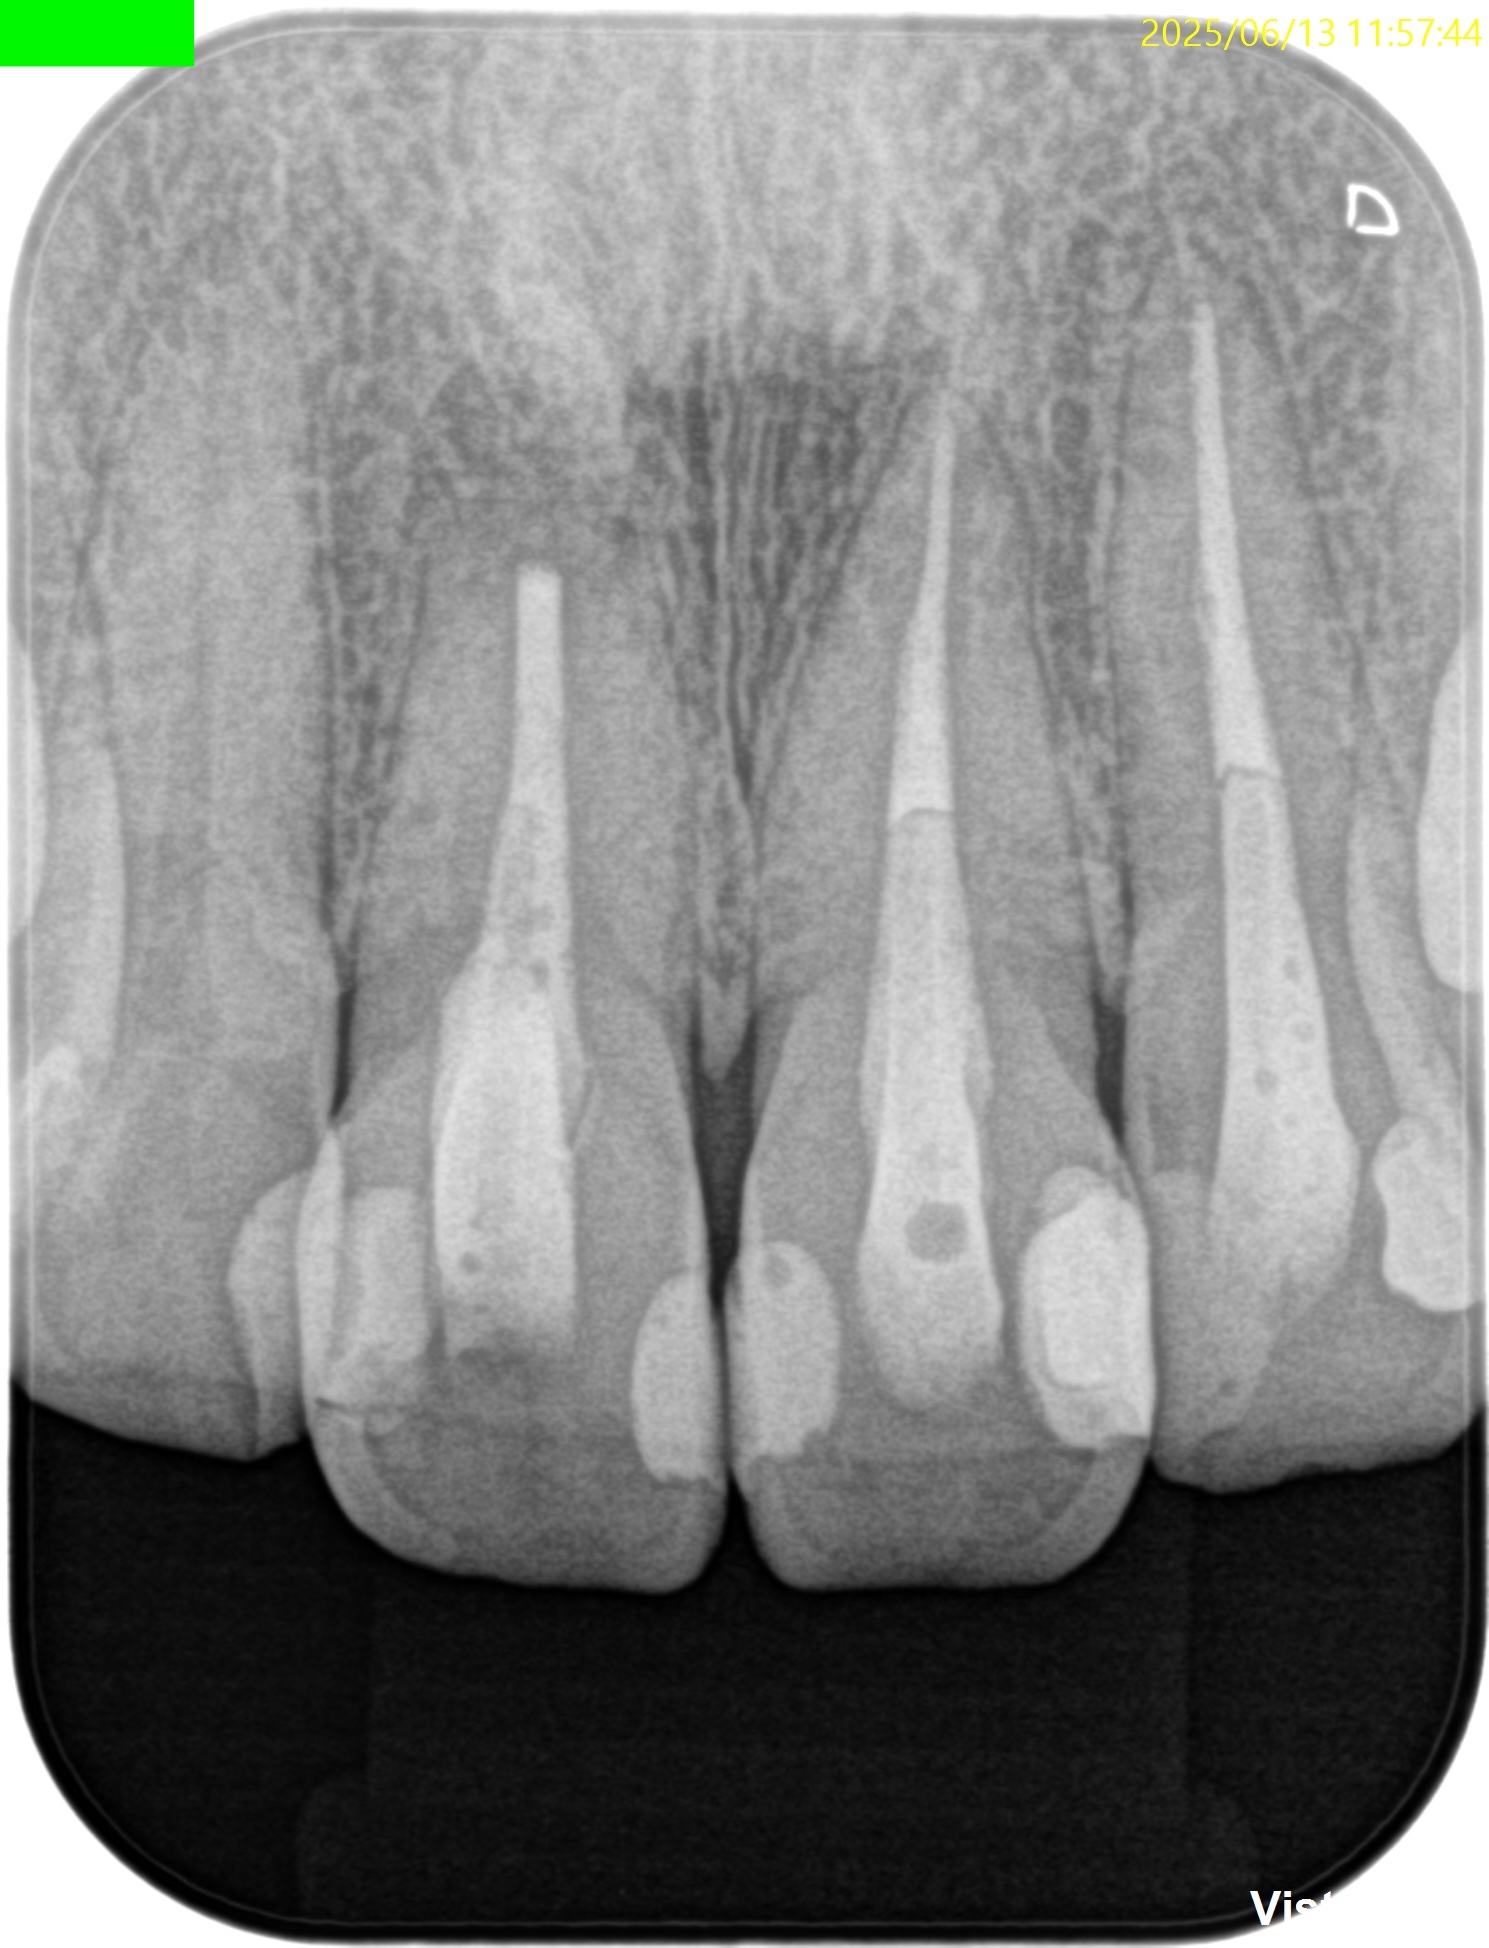

PA(2025.6.3)

#8,9,10ともに全く根管治療が不適切としか言いようがない。

#8はForamen付近の形成が太そうだ。